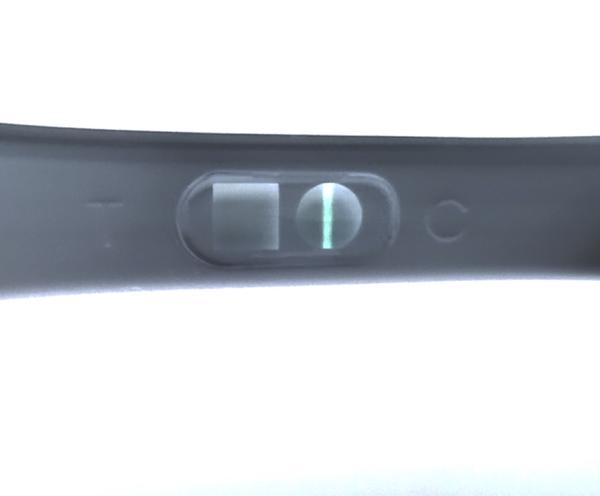

@wewe28 ahojky, to iste ako minuly týždeň, slabý ružový duch na 25kovom teste, na 10kovom ani náznak, cecky už o číslo väčšie ako zvyčajne, ráno nevoľnosť ako hovado, biely hustý výtok bez zápachu, fakt tomu nechápem... no a keď berieme od spinenia je to 13 dni, keď to berieme že to bola MS (čo podľa mna nebola) tak 13 DC, zajtra začínam poslednú krabičku Duphastonu a potom kontrola u gynekológa..prikladám fotky ale nemyslím si že to na mobile vidno, je to viac vidno voľným okom aj po rozobratí ale cez mobil nie. Španielska dedina toto, ale asi sa na to vykaslem len ide Silvester a neviem či si teraz dať pozor s alkoholom alebo nie

No nič tam nieje vidno ale ! Ak si tehotná druha čiarka silnie tak počkaj a správ si test neskoršie 🙂

@wewe28 však práve, že to by som bola riadne na hlavu pokladať to spinenie za MS nakoľko to nič nebolo...ešte ma napadlo ako som tu čítala že niektorým neukázal tehu test do 8-9 týždňov 2 čiarky čo by vysvetľovalo moju situáciu ale to by bolo už plne fantázie takze to neberiem ani do úvahy, možno sa mi búria hormóny, kto vie prečo tie nevoľnosti a plne cecky apod 😂 gynekológ neordinuje medzi sviatkami, takze krv vylúčená...ale muž ma “prekvapil” dvoma testami (chudák nevedel čo kupuje, sú to 25ky) ktoré si MUSÍM zobrať na chatu a testnut na Silvestra, ale povedala som mu, že nech s tým konečne prestane a nič na tom teste nie je a koniec, ideme ďalej...a na Silvestra budem toľko piť, koľko mi povie telo - lebo ak som aj tehotná (fantazírujme) tak si telo aj tak povie nevoľnosťami...iné ma nenapadá, svet sa nezrúti 🙂

@reyka poznám aj také prípady. Možné je všetko a naše telo si často s nami robí čo chce. Tiež sa mi stalo že meškala potvora a zvracala som a nič z toho nebolo. Teraz mi prišlo raz zle po tých šiestich dní meškania a inak mi nič nebolo, len ten hlien sa mi mezdal a kukaj ako to vyšlo 😉 Pekne si ešte oddýchnite a neboj, raz sa to podarí. Možno keď to budeš najmenej čakať 😘